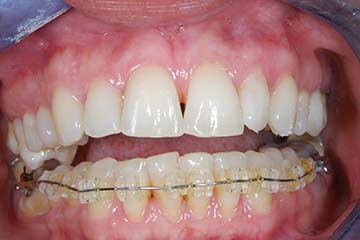

I denti irrecuperabili dell'arcata superiore ed inferiore del paziente di anni 65

sono stati sostituiti da 10 impianti, cioè protesi radicolari endo-ossee che sostengono le protesi fisse superiore ed inferiore.